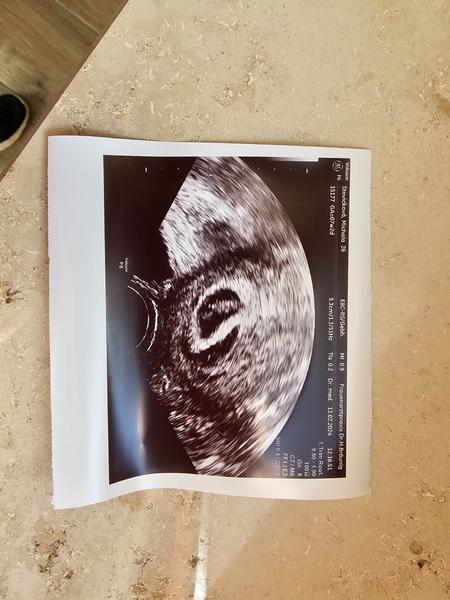

Ahoj, tak konečně srdecni akce ale udělal se hematom kolem delohy cca 2cm. Dneska jsem slabé krvácela.